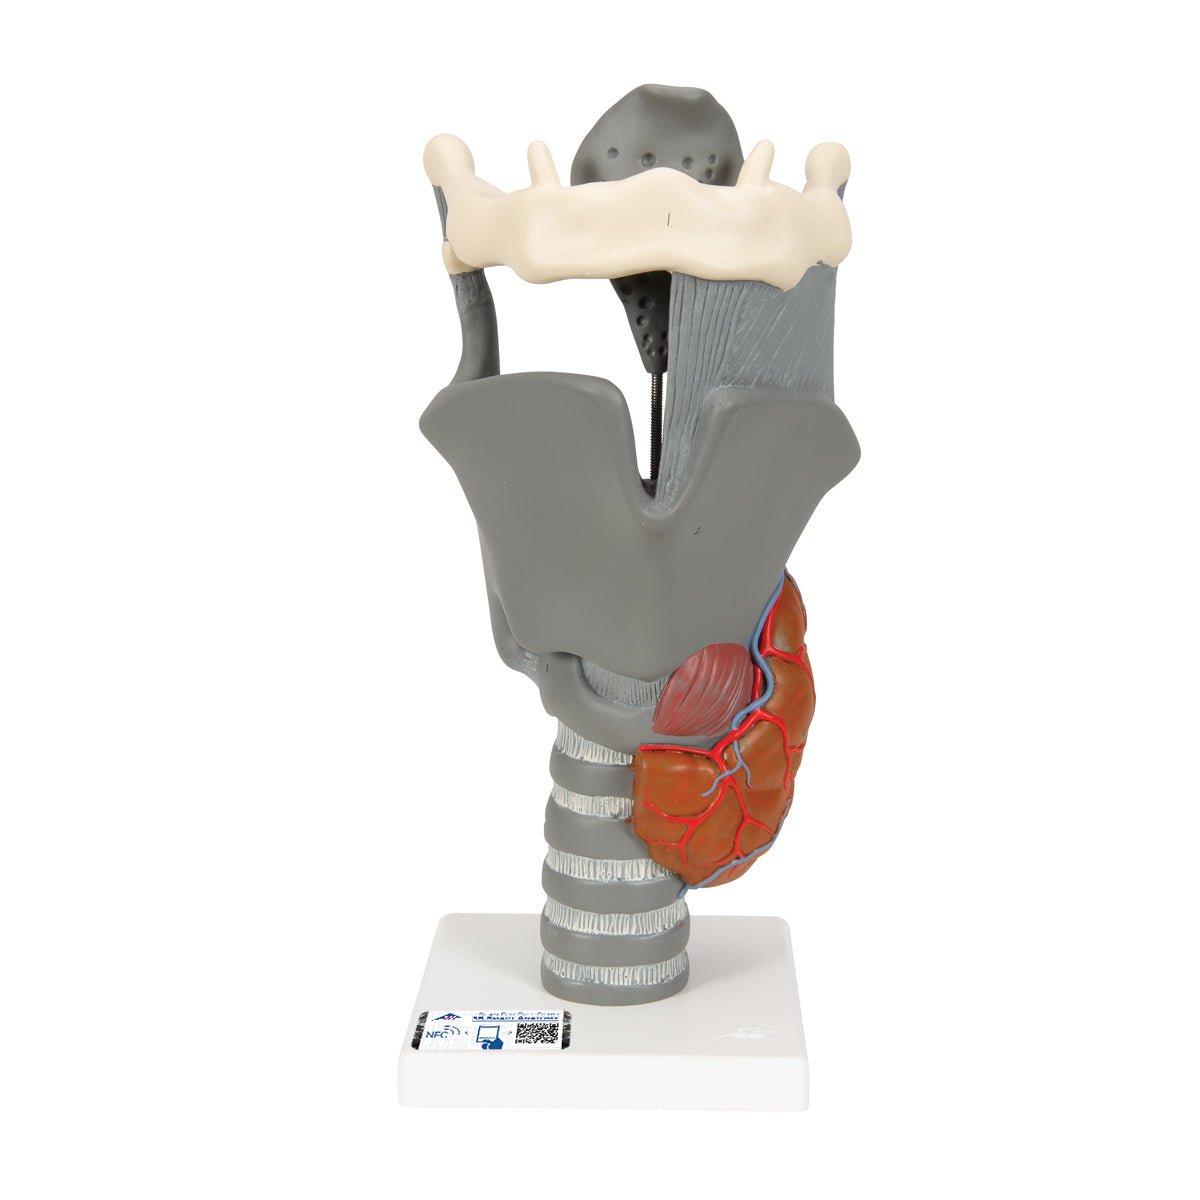

Salg af anatomiske modeller er det bærende element i eAnatomi, selvom vi også bruger mange ressourcer på at udvikle vores egne anatomiske materialer som fx plakater. Anatomiske modeller anvendes til forskellige formål og kan både vise afgrænset væv, organer samt organsystemer. Søger du en simpel model af knoglevæv eller måske en avanceret torso-model baseret på MRI teknologi, kan du finde det hele på eanatomi.com.